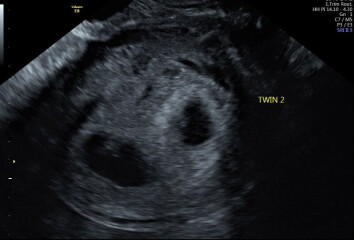

Hey OP, sorry you've not had a response to this yet! Hard to say, really. I learned I was having twins at my 6wk scan - Twin A was measuring 6w6d and Twin B was 6w3d. Here are some pics from my scan which may help you to compare against. You can see B's sac is quite a bit smaller.